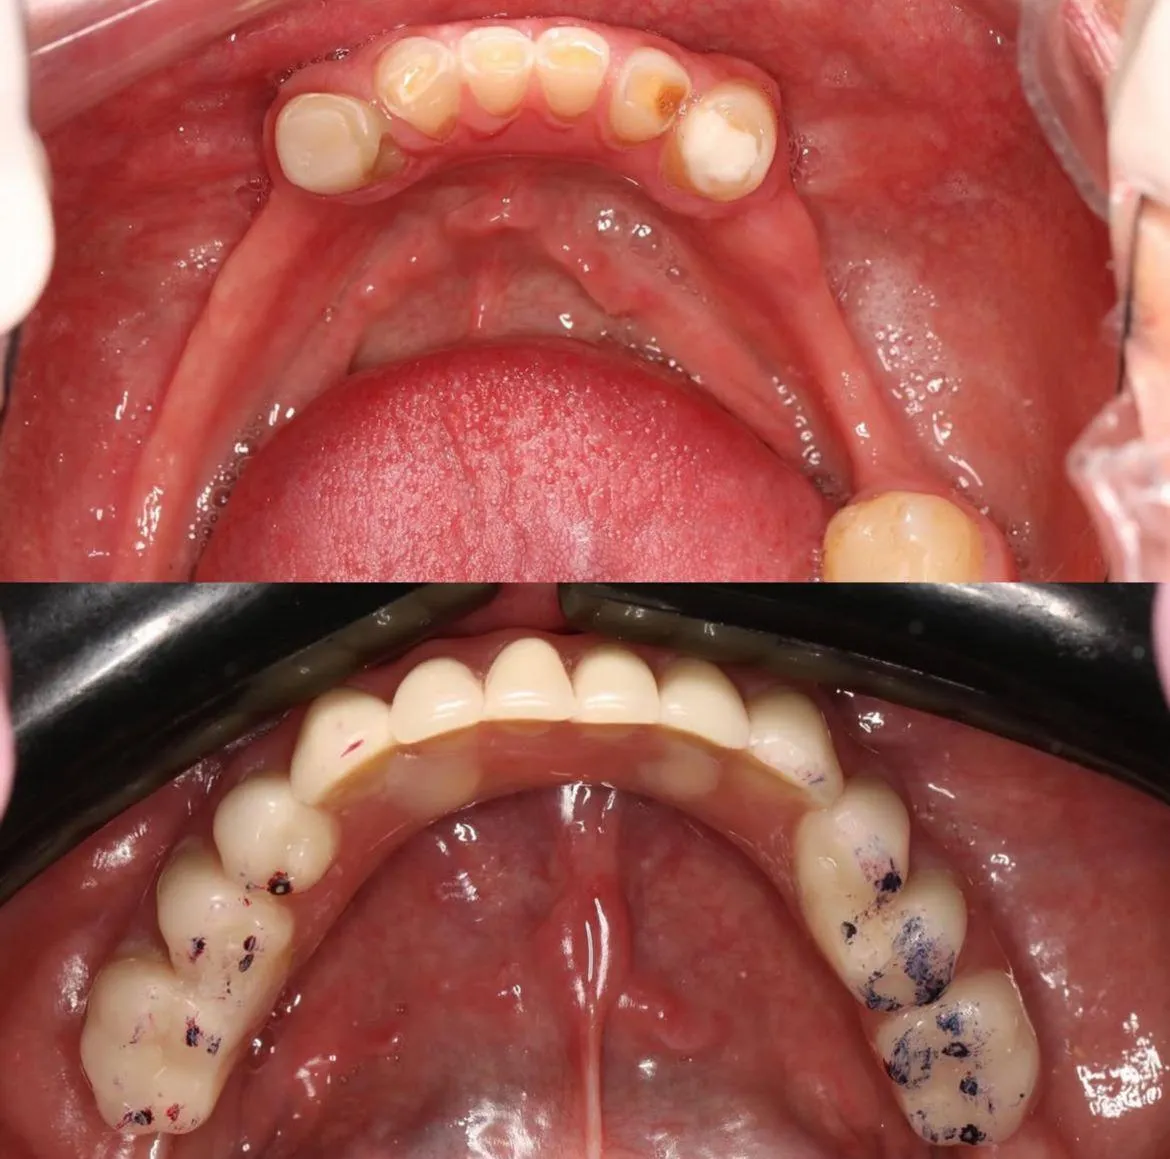

Cada historia es única. Aquí algunas transformaciones que nos llenan de orgullo.